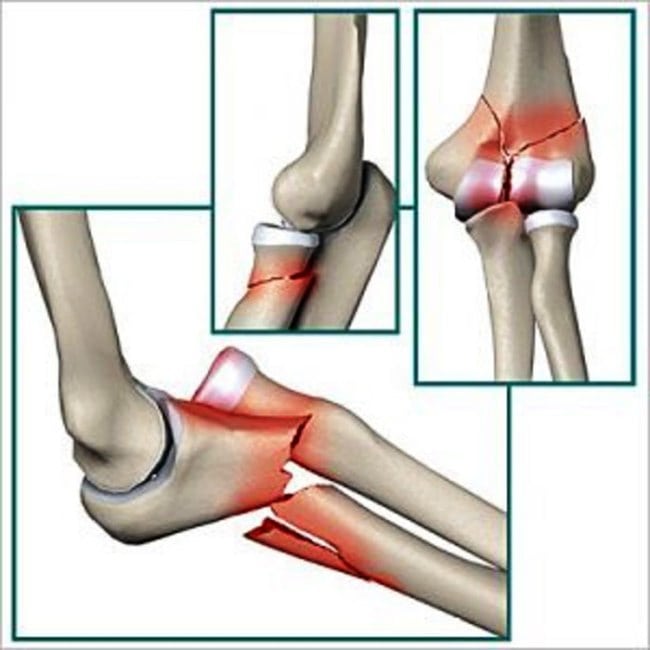

При установлении внутрисуставного перелома прогноз на полное выздоровление хуже. Задачами терапии становится качественное совмещение отломков и восстановление хрящевых поверхностей. Чаще всего диагностируются следующие травмы:

- переломы плечевых костей в области их головчатых возвышений. Отломки смещаются внутрь суставов, ограничивая их функционирование. Травмирование часто происходит при падении с упором на вытянутую руку или при вывихе. Пациентам показана хирургическая терапия. Крупные отломки закрепляют винтами в правильном положении. Маленькие фрагменты, не подлежащие репозиции, удаляют;

- травмы чрезмыщелковые, межмыщелковые. Это самые часто диагностируемые виды переломов, обычно возникающие при сильном ударе в локоть. Поддерживающие надмыщелки костные структуры разрушаются, что становится причиной изменения соотношения костей. Для таких травм характерно серьезное повреждение хрящевых тканей, восстановление которых является сложной задачей. После репозиции суставных элементов они крепятся винтами и пластинами до полного их сращения. Это не станет ограничением для постепенной разработки сустава.

Во время диагностирования оценивается состояние кровеносных сосудов, степень кровоизлияния в суставы. При проведении операции хирургу приходится восстанавливать и поврежденные нервы. Если этим этапом пренебречь, то разовьются тяжелейшие осложнения. Нарушение иннервации спровоцирует потерю чувствительности кисти, также возможно значительное снижение объема движений в локте.